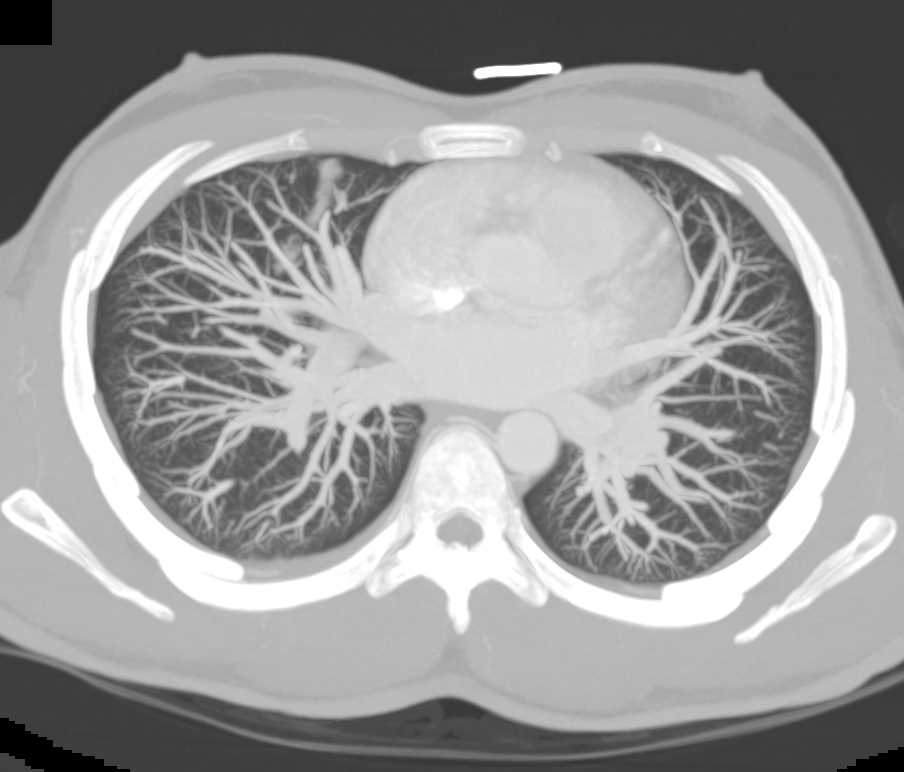

Small Right Pneumothorax Post Biopsy